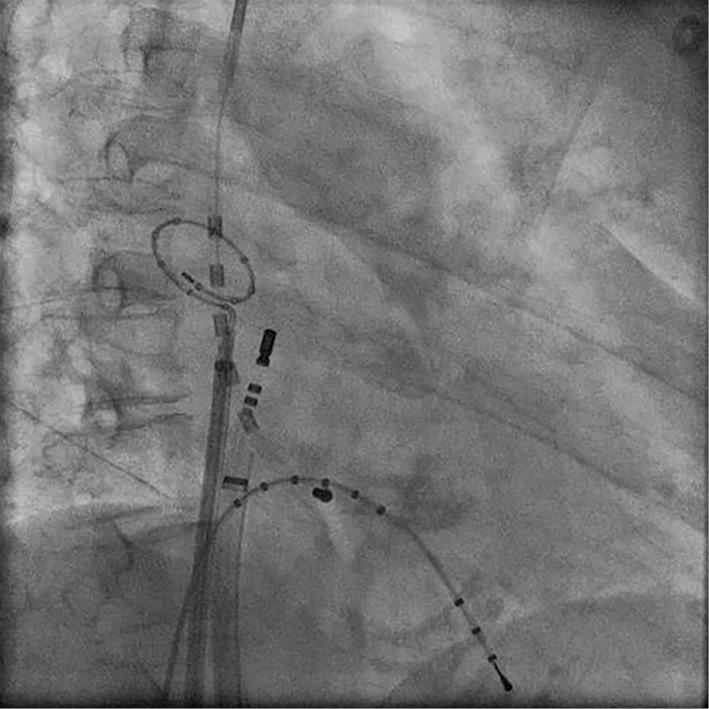

AF Sustained in Only a Small Area of SVC.